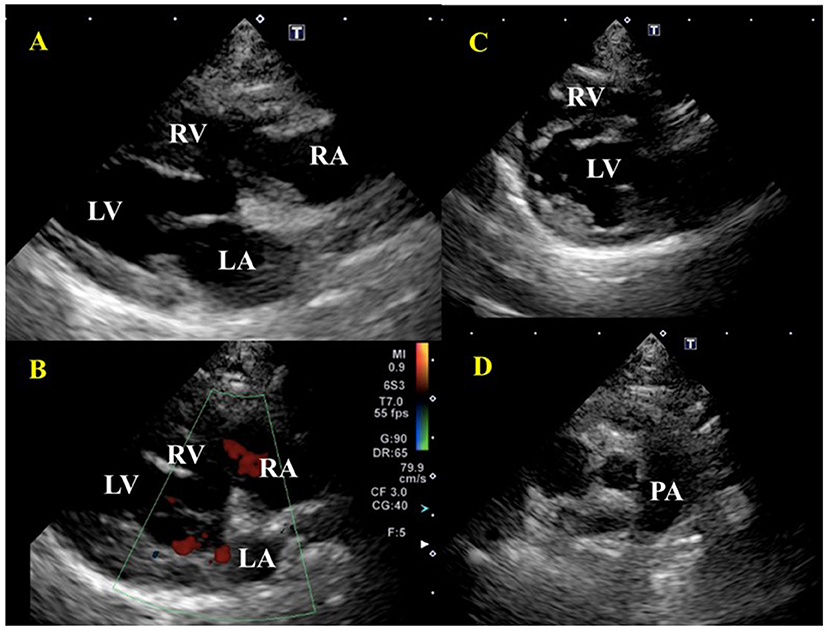

FIGURE 3

Figure 3. Echocardiographic images before treatment of a cat diagnosed with IMHA and pulmonary thromboembolism. (A) Right parasternal long-axis view. Enlargement of the right atrium and right ventricle were found. There was no dysplasia of the tricuspid valve, patent ductus arteriosus, atrial septal defect, or ventricular septal defect. (B) Right parasternal long-axis view (Color Doppler imaging). Tricuspid regurgitation was recognized. (C) Right parasternal short-axis view (Apical level). The flattening of the interventricular septum was observed. (D) Right parasternal short-axis view (Basal level). A thrombus was found between the main pulmonary artery and the bifurcation of the right and left pulmonary arteries. RA, right atrium; RV, right ventricle; LA, left atrium; LV, left ventricle; PA, pulmonary artery. Red arrows indicate a thrombus; white arrows indicate tricuspid regurgitation (TR).

Laboratory examination revealed severe regenerative anemia, increased white blood cell count, and decreased platelet count (ProCyte Dx Hematology Analyzer, IDEXX Laboratories, Japan). In addition, the auto-agglutination of red blood cells on the slide was observed (Figure 1). Blood chemistry tests showed elevated total bilirubin and phosphorus concentration (DRI-CHEM 7000V, Fujifilm, Japan). Blood coagulation tests are also shown in Table 1 (PT, APTT, Fib). The blood fibrinolytic system test revealed a normal D-dimer level (Fujifilm Monolith, reference value: 0–2.0 μg/ml). The blood type was determined to be type B. There was no evidence of infectious disease-causing hemolytic anemia: negative feline vector-borne pathogens (FeVBPs), feline leukemia virus antigen (FeLV), and feline immunodeficiency virus antibody (FIV) tests (IDEXX Laboratories, Japan). Also, the antiglobulin antibody (Coombs test, Fujifilm Monolith, Japan) and the anti-nuclear antibody test (IDEXX Laboratories, Japan) were negative. On thoracic and abdominal radiographs, the right lateral view showed the increased pulmonary opacity in the anterior lung lobes and the disappearance of the ventral waist of the cardiac shadow, suggesting right heart enlargement and pulmonary edema (Figure 2A). In the dorsoventral view, the interlobar fissure in the posterior lung lobe was clear, suggesting pleural effusion (Figure 2B). Abdominal radiography showed no significant alteration. Echocardiography revealed an enlarged right ventricle and right atrium with tricuspid regurgitation (TR flow 3.28 m/s) in the right parasternal long-axis view (Figures 3A,B). The right parasternal short-axis view showed flattening of the interventricular septum on B-mode images (Figure 3C). In the right parasternal short-axis view at the base of the heart, dilatation of the main pulmonary artery was observed (PA/Ao 1.1), and the pulmonary arterial flow velocity was 0.8 m/s with a shortened acceleration time to ejection time ratio (AT/ET 0.25). Hyperechoic structure, which was suspected thrombus, was observed in the pulmonary artery bifurcation (Figure 3D). Early diastolic mitral inflow (E wave) was 0.5 m/s. Right ventricular fractional area change (RV-FAC) was 18%, obtained by tracing the RV endocardial border at end-diastole and end-systole from the left parasternal long axis 4-chamber view. The right atrial area (RAA) was 2.75 cm2, measured by tracing from the lateral aspect of the tricuspid annulus to the septal aspect, excluding the area between the leaflets and annulus, following the RA endocardium at the end of the ventricular systole. A small amount of pleural effusion was observed, however, thoracentesis was not performed due to the low platelet count and bleeding tendency. There was no evidence of short-circuit disease or structural abnormality of the tricuspid valve. Abdominal ultrasonography showed a trace amount of ascites which was difficult to collect. There were no other significant findings, and no tumor lesions were observed.